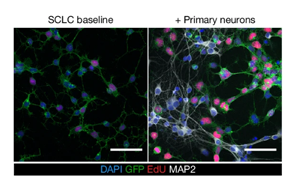

神經(jīng)元活動依賴性機制驅(qū)動小細胞肺癌發(fā)病機制的新見解

本文揭示了神經(jīng)元活動在小細胞肺癌(SCLC)發(fā)病機制中的關鍵作用。研究表明,在腦內(nèi),谷氨酸能(glutamatergic)和GABA能(GABAergic)神經(jīng)元通過旁分泌和突觸相互作用促進SCLC增殖;在肺內(nèi),迷走神經(jīng)支配對原發(fā)性腫瘤發(fā)展至關重要。該發(fā)現(xiàn)為靶向神經(jīng)-腫瘤互作提供了新的治療策略。